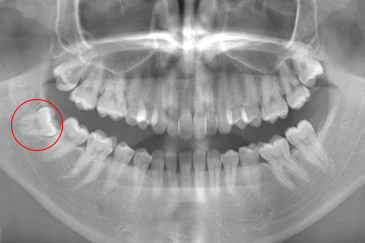

現在の治療費と異なる場合がございます。最新の治療費は料金表をご確認ください。CASE 1

事前にCT撮影を行い神経との位置関係を確認して抜歯を行いました。右下親知らずは歯ぐきの中に完全に埋まり、

また斜めに生えていた為歯ぐきを切って親知らずの頭部分を分割して抜きました。

翌日多少の腫れが見られましたが痛みも痛み止めを飲めば過ごせる程度で出血はほとんどありませんでした。

抜歯前

抜歯後

基本情報

| 年齢・性別 | 24歳・女性 |

|---|---|

| 主訴 | 右下の親知らずが抜きたい |

| 治療内容 | 完全埋伏抜歯 |

| 治療期間 | 60分 |

| 治療費 | 約8,000円 |

| リスク・副作用 | 2〜3日は腫れと痛みがある。 必要に応じて抜歯を2回に分けて行う場合がある。 |